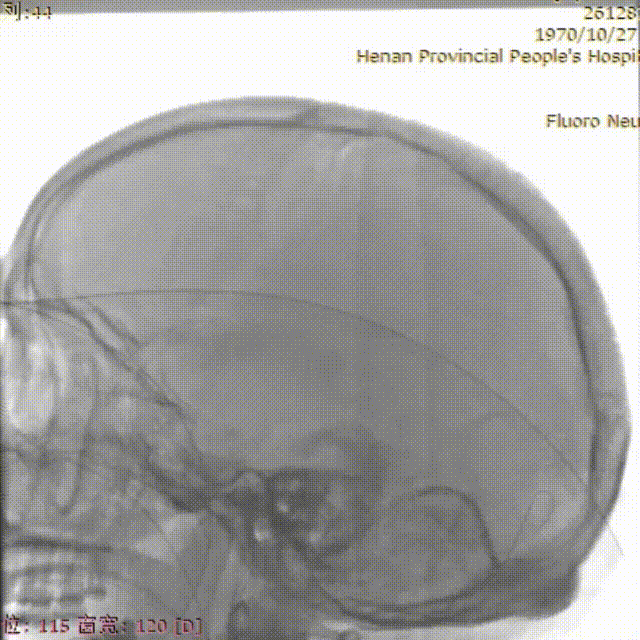

CT显示左侧顶叶低密度水肿影,内见高密度血肿影;上矢状窦高密度,考虑上矢状窦血栓可能大。